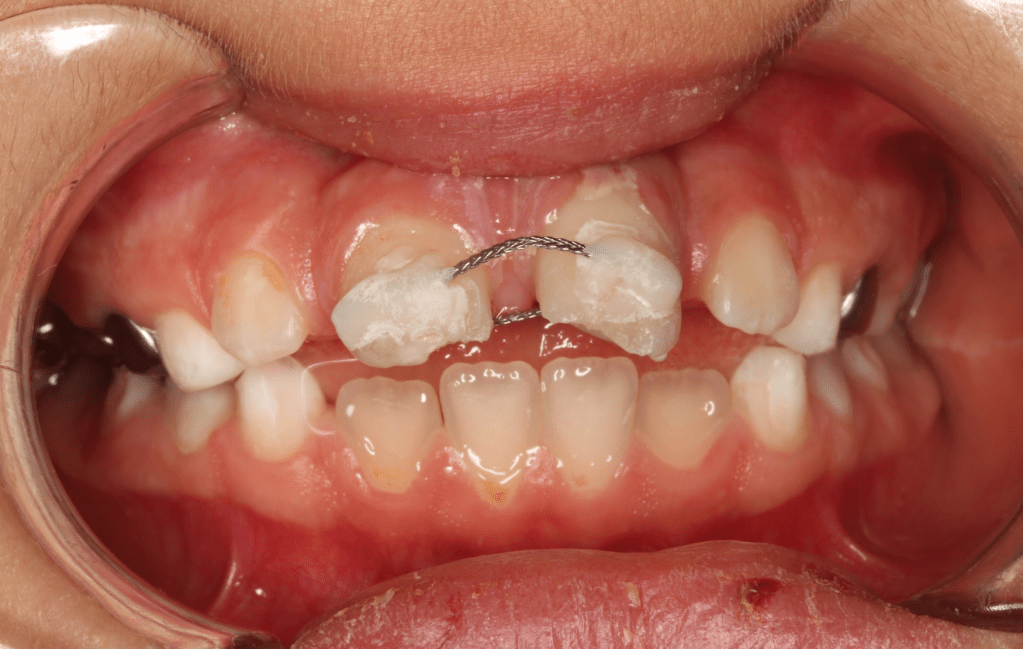

Fractura con exposición pulgar

Reconstrucción con recubrimiento pulgar indirecto